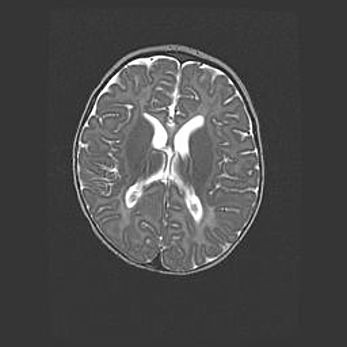

Сообщающаяся гидроцефалия. Кистозная энцефаломаляция головного мозга.

Возраст: 3 месяца 4 дня

Вес: 3100 г

Пол: женский

Окружность головы: 34 см

Срок гестации: 31 неделя

Кистозная энцефаломаляция головного мозга - одна из форм поражения головного мозга в детском возрасте. Характеризуется возникновением множественных и распространённых кист в коре, белом веществе и подкорковых образованиях головного мозга у плодов, новорождённых и детей раннего возраста. Развитие кистозной энцефаломаляции связано с внутриутробной асфиксией и гипотонией, родовой травмой, тромбозом синусов, пороками развития сосудов, инфекциями, сепсисом и другими причинами. Наиболее значимые инфекционные агенты: вирусы простого герпеса, цитомегалии, краснухи, токсоплазмы, энтеробактерии, золотистый стафилококк и другие.